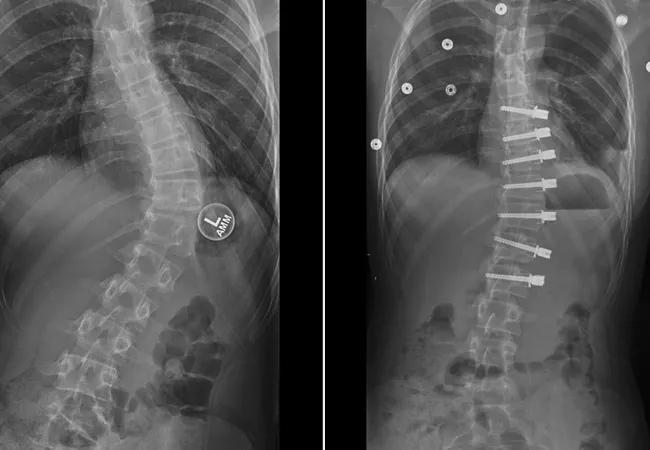

Progression of scoliosis correction with vertebral body tethering

Progression of scoliosis correction with VBT. A. Spinal curve in a 13-year-old patient with idiopathic scoliosis. B. Initial radiograph after VBT surgery, displaying partial correction of the curve. C. Continuing correction of the spinal curve six months after surgery. D. Further correction of the spinal curve 18 months after surgery.